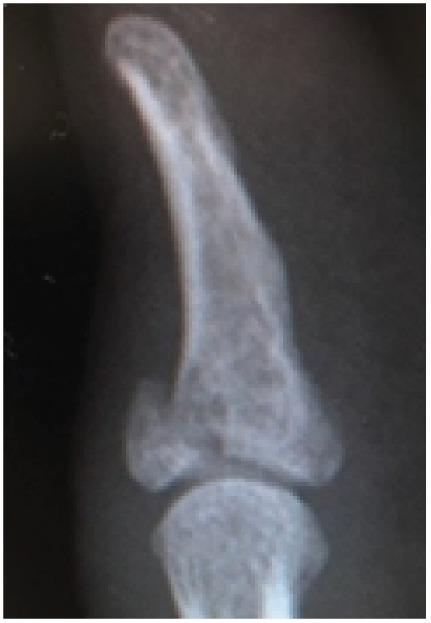

Bony mallet is a common sport injury, but bony mallet thumb is rarely encountered. We performed open reduction and fixation of bony mallet thumb using a hook plate procedure on a 27-year-old man under general anesthesia. The patient began working one day after surgery. Six months postoperatively, the patient had excellent dexterity according to Crawford's evaluation criteria and no difficulties at work or playing softball. Tension band fixation, compression pins, and the extension block technique are commonly used to manage bony mallet. Despite the anatomical reduction, rigid fixation, and early resumption of motion skills offered by the hook plate technique, to our knowledge, no previous reports of its application to bony mallet thumb were found. In this case, the hook plate technique was chosen and made an early return to work possible and brought about a successful result.

锤状指是一种常见的运动损伤,但拇指锤状指很少见。我们在全身麻醉下,对一名27岁男性采用钩钢板手术对拇指锤状指进行了切开复位内固定。患者术后一天就开始工作。术后六个月,根据克劳福德评估标准,患者的灵活性极佳,工作或打垒球时均无困难。张力带固定、克氏针和延长阻滞技术常用于治疗锤状指。尽管钩钢板技术提供了解剖复位、坚强固定和早期恢复运动技能,但据我们所知,此前尚无其应用于拇指锤状指的报道。在本病例中,选择了钩钢板技术,使患者能够早日重返工作岗位并取得了成功的结果。